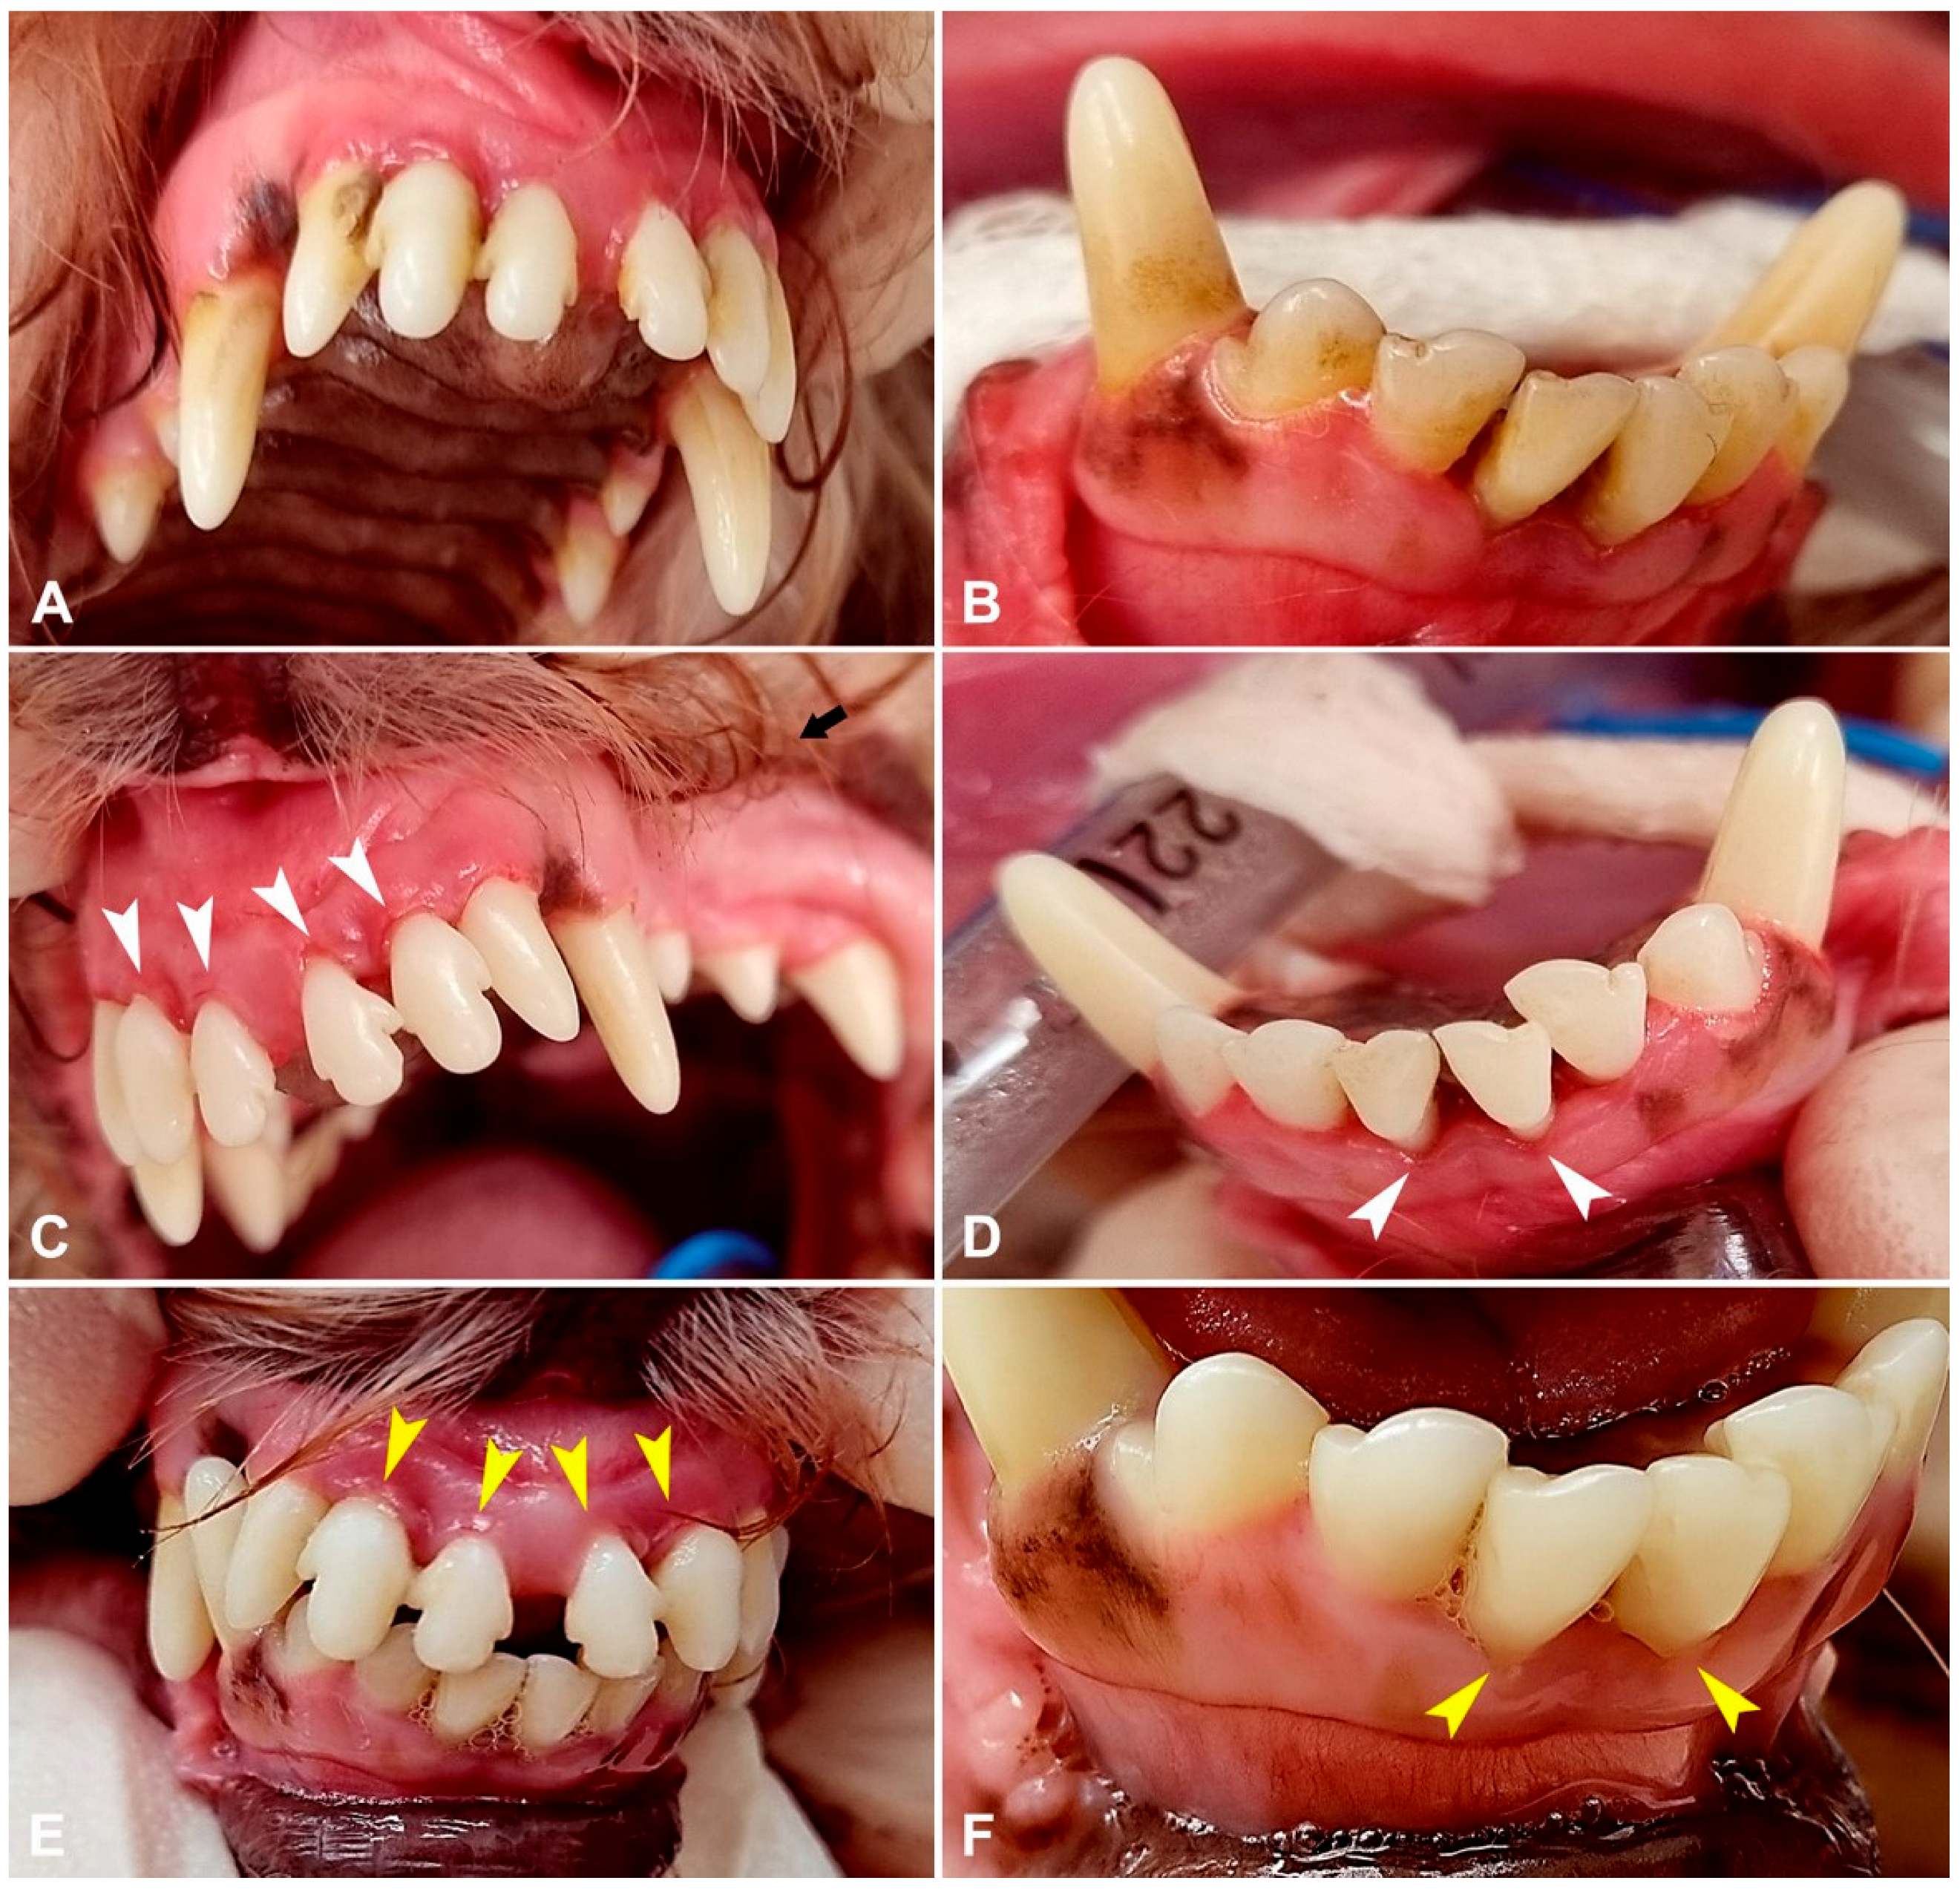

3. Results

3.2. Periodontal Parameters